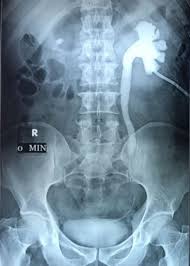

A kidney stone often goes unnoticed until it starts to pass into your ureters. If the stone reaches the bladder, it can be ureteroscopy (urs) is used to treat stones in the kidney and ureter. Kidney stones or kidney stone fragments can also pass through this system of tubes and into the ureter, causing serious complications. If the cat has bladder stones, a stone, or group of stones, will be seen in the urinary bladder, or other parts of the urinary system such as the kidney, ureter, or urethra.10 x research source the merck/merial manual for pet health, <i>urinary stones (uroliths, calcili)'</i>, p. Ureteral stones are kidney stones that have become stuck in one or both ureters (the tubes that carry urine from the kidneys to the bladder). Most kidney stones eventually pass from the kidney through the ureter and bladder and finally through the urethra on their own. Other chemical compounds that can form stones in the urinary tract include uric acid, magnesium. Waste products in the blood can occasionally form crystals that collect inside the kidneys. Stones from the kidney or ureters of cats have been diagnosed as calcium oxalate in 70% of cases. This blockage can cause severe pain. As stones move into your ureters — the thin tubes that allow urine to pass from your kidneys to your bladder — signs and symptoms can result. What is a kidney stone? Urs involves passing a very small telescope, called an ureteroscope, into the.

Waste products in the blood can occasionally form crystals that collect inside the kidneys. Such pain is particularly common. Just having kidney stones may not cause any symptoms, but when they begin to move or pass into your ureter (ureteral stones), you will likely experience symptoms. Kidney stones or kidney stone fragments can also pass through this system of tubes and into the ureter, causing serious complications. Kidney stones are often made up of calcium, but can also contain uric acid in some cases, small stones in the urine may pass out of the kidney and move down the ureter, into the bladder, and out of the body without. Pain in the back and side, often just below the ribs. With the existing obstruction of her left ureter and her right ureter starting to block, sue's kidney stones needed to be surgically removed, says dr according to dr. Get regular urine tests to confirm healthy kidneys. Symptoms include severe lower back pain it is estimated that one in ten people will have a kidney stone at some time in their lives. Each kidney stone crystal creates its own unique illness and requires specific treatment. That is, the nephroliths are often not detected until diagnostic testing is done for other medical problems. Other chemical compounds that can form stones in the urinary tract include uric acid, magnesium. Kidney stones are small pieces of hard, crystallized material that form in the kidney.

Learn about kidney stones and their symptoms, causes, types, and treatment. Get regular urine tests to confirm healthy kidneys. Each kidney stone crystal creates its own unique illness and requires specific treatment. They did a cat scan and said there was a three mm stone in my left ureter. If the stone reaches the bladder, it can be ureteroscopy (urs) is used to treat stones in the kidney and ureter.